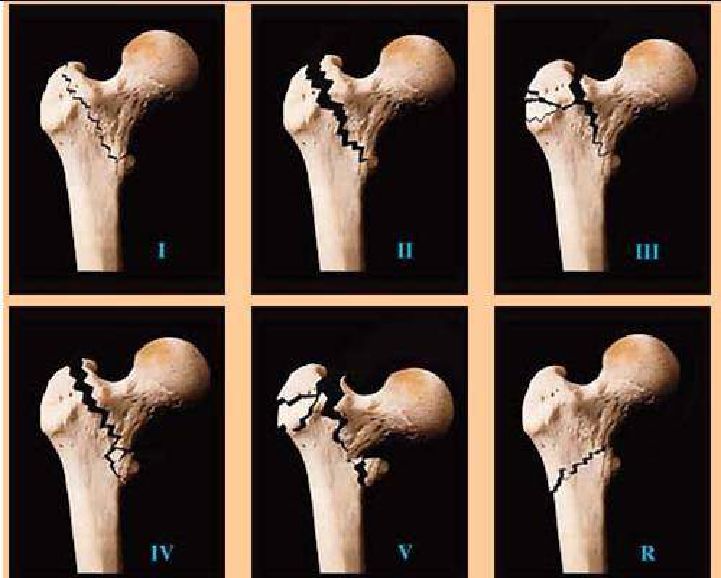

Les fractures AO et Evans-Jensen sont les deux types de fractures les plus couramment utilisés, et de ces deux, le type de fracture AO est le plus courant.

Type I : Fracture intertrochantérienne simple avec un trait de fracture en pente du supérieur vers l'inférieur, sans déplacement ni stabilité.

Type II : Déplacement associé à une petite fracture par avulsion du rotor, mais l'éperon fémoral est intact (l'éperon fémoral est une plaque osseuse dense située profondément à l'intérieur du col fémoral et de la jonction corps du petit rotor.

Type III : Fracture combinée du grand trochanter avec accumulation de fracture de l'éperon fémoral, avec déplacement, souvent avec fracture interrotor postérieure.

Type IV : Fracture en 3 parties associée à une fracture comminutive du petit trochanter, pouvant se présenter avec une fracture éclatée du col fémoral et de la face coronale du grand trochanter.

Tapez V : fracture postérieure latérale et médiale sans appui (combinaison des types III et IV).

Tapez R : une fracture intertrochantérienne antérieure avec une ligne de fracture oblique du médial supérieur au latéral inférieur, qui peut être associée à une petite fracture du rotor et à une destruction de la colonne fémorale.